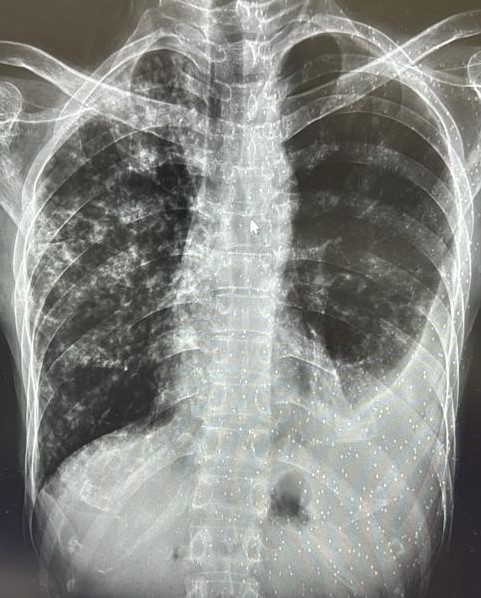

| 338 | IGGMC, Nagpur, Nagpur | P2 | 29-4134 | Rupesh Dongse | Consent taken on Paper | 43 Yrs. |

Provisional Diag : Consolidation

Final Diag : Bilateral Consolidation Community Acquired Pneumonia With Type 1 Respi Failure In Cronic Alcoholic |

Non-TB Case (Confirmed) | Bilateral Consolidation | Abnormality visible on x-ray |